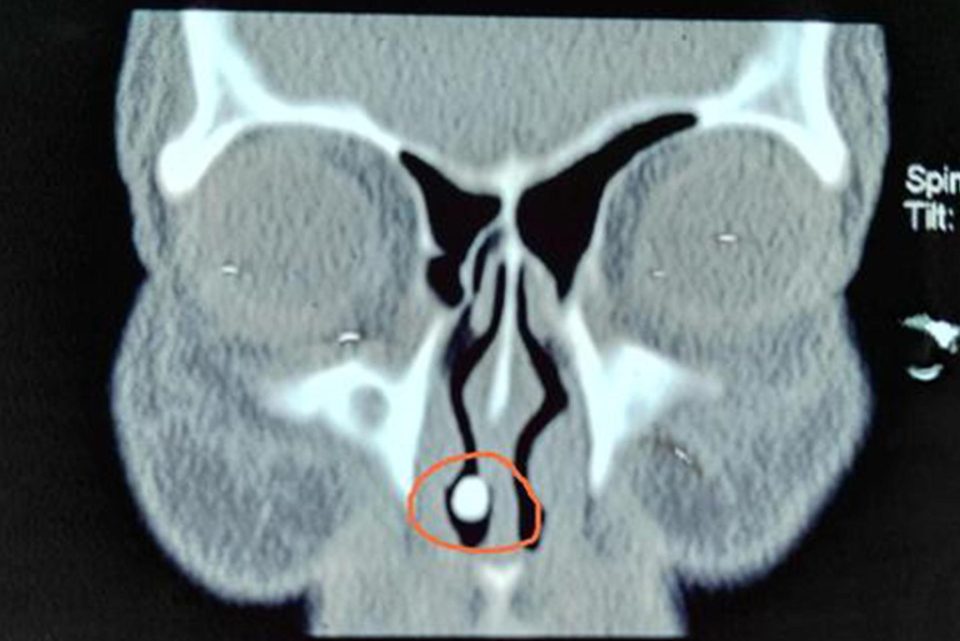

“Kết quả chụp cho thấy có bóng đen đặc ở khoang mũi phải. Chúng tôi nghĩ đó là một vật lạ hoặc một dạng cứng như đá”, bác sĩ Zhou Jianpo nói.

Sau khi phẫu thuật, các bác sĩ lột bỏ lớp màng và bất ngờ khi thấy một chiếc răng mọc đầy đủ với chân răng bên trong khoang mũi. Theo bác sĩ Zhou, đây là hiện tượng răng thừa, khiến cho răng mọc ở một vị trí nào đó khác trên khuôn mặt. Chiếc răng phát triển từ trong quá trình mang thai của người mẹ.

Vị trí oái oăm của chiếc răng “mọc lạc”.